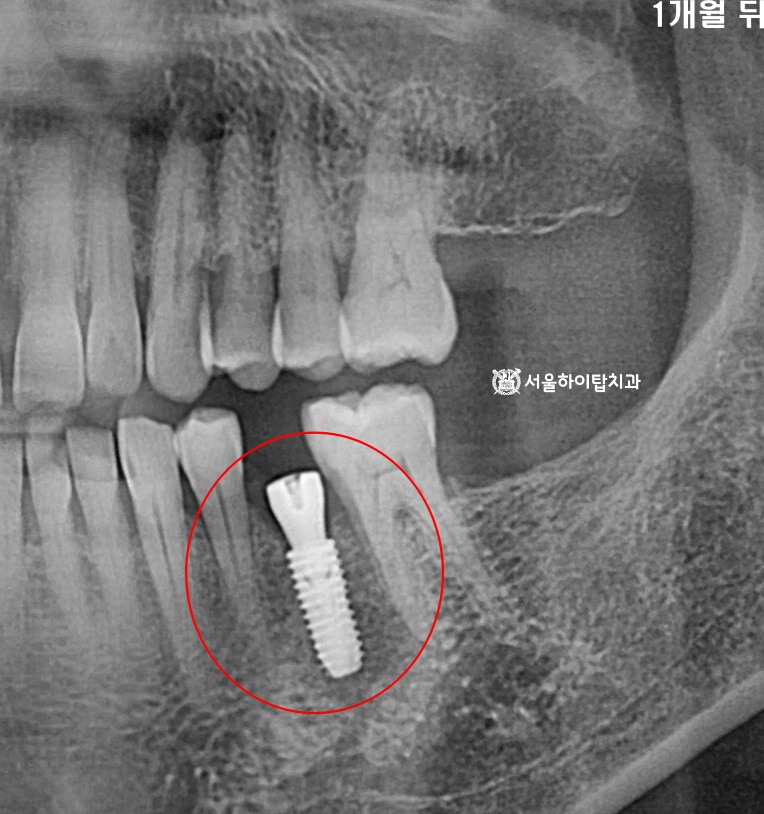

식립 후 약 한 달 뒤에는 경과 관찰(Follow-up)을 진행하여

픽스처의 초기 골유착 상태와 주변 연조직 치유 양상을 확인합니다.

간석오거리역 치과 에서는 이 시기에는 동요도 여부, 통증 유무,

방사선 사진을 통한 변연골 변화 등을 종합적으로 평가하게 된다고 말씀드립니다.